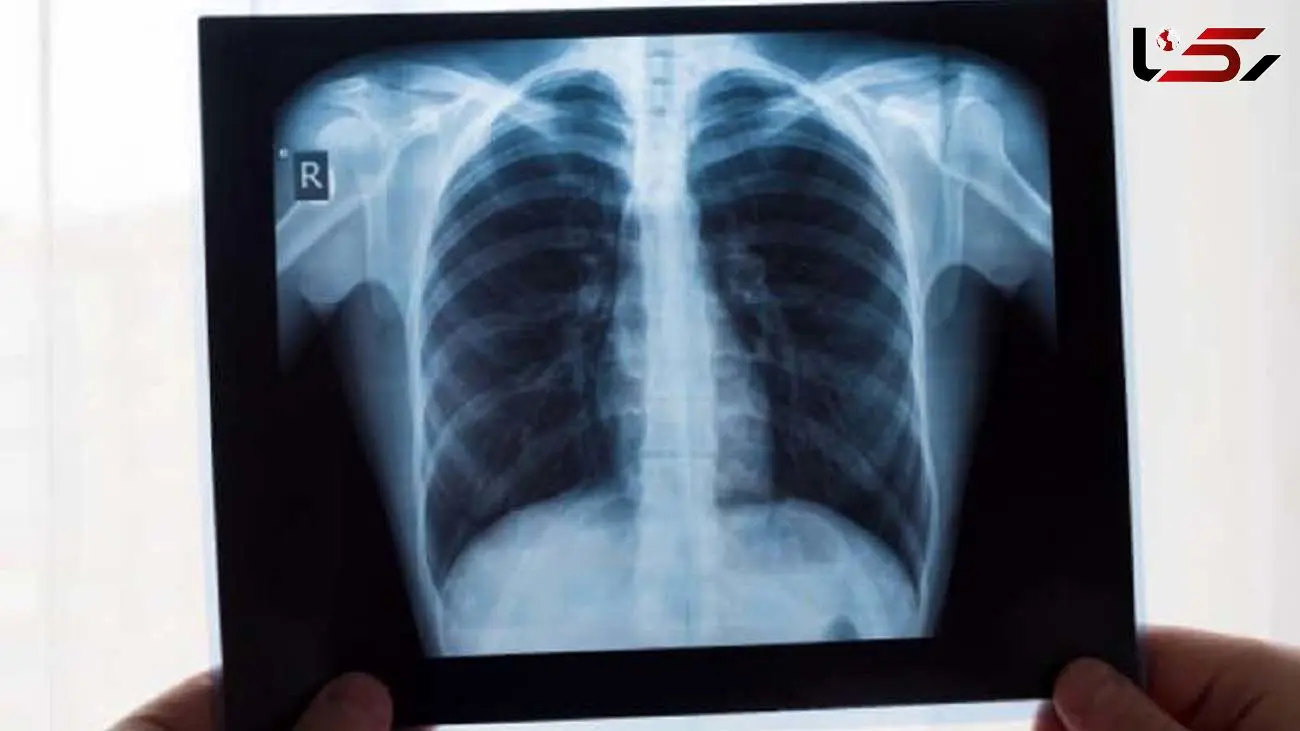

معمولاً در ناحیه آسیب دیده کبودی قابل مشاهده است. تشخیص قطعی توسط x-ray  و سی تی اسکن و اسکن استخوانی امکان پذیر است. همچنین از MRI  نیز برای مشاهده بافت های نرم و اندام های اطراف دنده ها مانند ریه استفاده می شود.